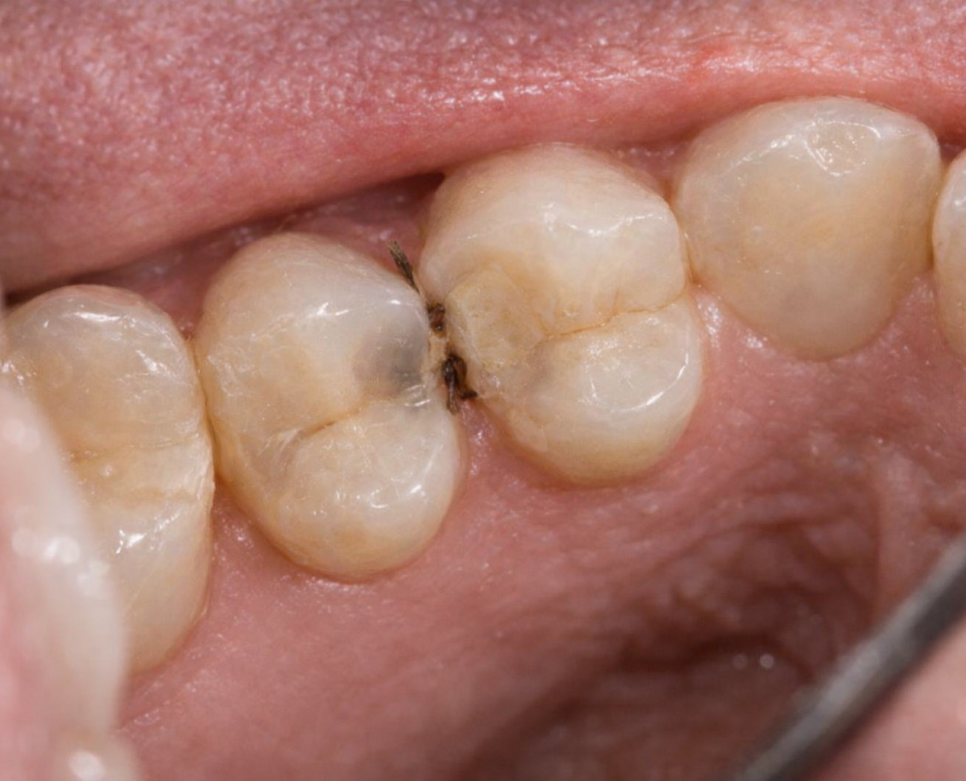

치아와 치아가 서로 맞닿아 있는 옆면,

즉 인접면(Proximal surface)에서

발생하는 충치를 의미합니다.

이 부위는 구조적으로

칫솔모가 닿기 어렵고

음식물 잔사와 치태(plaque)가

쉽게 남을 수 있는 환경이기 때문에

충치가 발생하기 쉬운 조건을 가지고 있습니다.

또한 치아가 서로 밀착되어 있는

구조적 특성 때문에

초기 충치가 발생하더라도

육안으로는 확인이 거의

불가능한 경우가 많습니다.

겉 보기에는 정상처럼 보이지만,

실제로는 치아 사이 내부에서

탈회와 충치 진행이

이루어지고 있는

경우도 많습니다.

인접면 충치가 까다로운 이유 중 하나는

초기에는 통증이 거의 없다는 점입니다.

겉으로는 확인할 수 없는

‘사각지대’에 해당합니다.

즉, 직접 볼 수가 없는 것이죠.

(위치, 크기에 따라 보이는 경우도 있습니다.)

더불어 초기에 뚜렷한 색 변화나

눈에 띄는 구멍이 생기지 않는

경우가 많습니다.